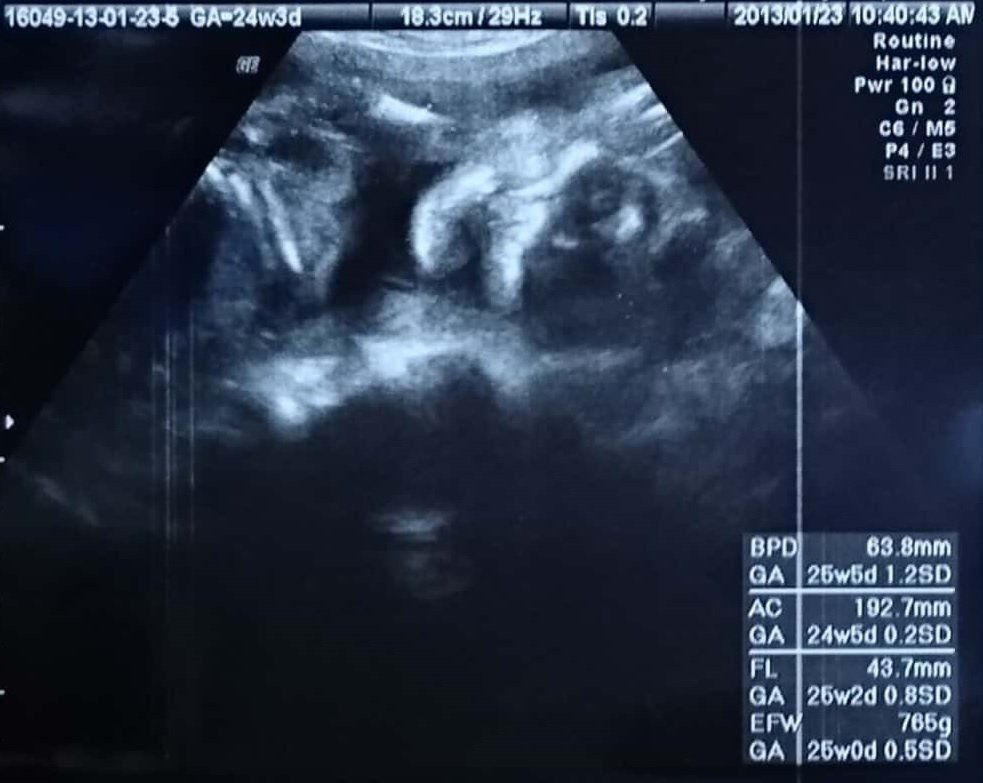

妊娠24週のエコー写真 夫が胎動を確認。胎動があると安心

FL(太ももの骨の長さ):43.7mm

再び、ホラーのような顔正面のエコー写真に。ちょっと前から胎動が始まっていましたが回数は少なく、夫が胎動を確認したのは数週間後でした。25週目の頃、突発的におなかに痛みが。ただ、おなかが張るような自分でも不安な感じがするものではなく、胎動もあったため、ネットの情報で“子宮が大きくなる痛み“だというのを信じて様子を見ました。すると、1日ほどで痛みはおさまりました。この頃になると、私にとって胎動は、赤ちゃんが元気に育っているという安心材料になっていました。